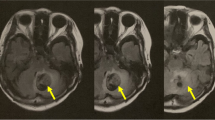

In the patient group, a significant association between contra-lesional stimulation and a decrease in CoP comp-score in the tandem position was found: β = − 0.25, CI = − 0.48 to − 0.03, p = 0.03. Post hoc analysis showed a significant decrease in ACoP: β = − 0.86, CI = − 1.58 to − 0.15, p = 0.02; varCoP: β = − 1.10, CI = − 1.93 to − 0.26, p = 0.01; range: ratio due to log transformation, β = 0.94, CI = 0.90–0.98, p = 0.01; and VCoP: ratio due to log transformation, β = 0.97, CI = 0.94 to 0.99, p = 0.02 but not in varVCoP: ratio due to log transformation, β = 0.97, CI = − 0.93 to 1.01, p = 0.11, see Fig. 4. The GEE-model constructed for the eyes open position revealed a significant association between ipsi-lesional stimulation and a lower CoP comp-score: β = − 0.09, CI = − 0.18 to − 0.01, p = 0.03; after correcting for randomization order, the association was no longer significant and changed to β = 0.00, CI = − 0.09 to 0.90, p = 0.94.

Effect of stimulation on tandem stance performance in stroke. Center of pressure (CoP) parameters measured during the pre-stimulation and post-stimulation in the subject-specific tandem stance (tandem) positions. The mean amplitude of the CoP (ACoP) and its amplitude’s variability (varCoP), and the velocity of the CoP (VCoP) and the velocity’s variability (varVCoP) and de composite-score are displayed. *Indicates a significant difference with a probability value of < 0.05, in the generalized estimating equation model with a correction for baseline and randomization order between contra-lesional cerebellar transcranial direct current stimulation (cb_tDCS) and the sham condition. Error bars indicate the standard error of the mean